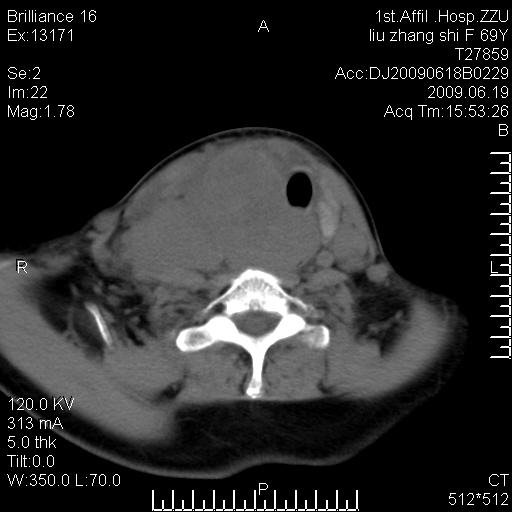

标题: CT26782:女,69岁,颈部占位,3天后公布病理结果。

【病理证实系列】女,69岁,颈部占位,有病理结果,3天后公布。(由于病例时间较久,临床资料不全,请网友见谅)本系列将有几百种常见、少见及罕见病例,均经病理证实。病例资料来自郑州大学第一附属医院。与网友共享,本人有空就发。

甲状腺癌并颈部淋巴结转移。感谢楼主的良苦用心,谢谢。

甲状腺癌并颈部淋巴结转移。

需与鼻咽癌鉴别!

支持甲状腺癌广泛侵及周围结构并颈部淋巴结转移。

鉴别:淋巴瘤、恶性神经源性病变、恶性纤维组织细胞瘤。

病理结果:颈部非霍奇金淋巴瘤。

右侧甲状腺确实有问题